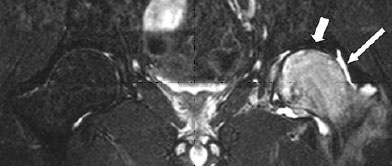

Μαγνητική Τομογραφία (MRI)

H Μαγνητική τομογραφία μπορεί να ανιχνεύσει τις οστικές μεταβολές πολύ νωρίτερα καθώς και να δώσει λεπτομερείς εικόνες της κατάστασης των περιβάλλοντων ιστών.

Επίσης μπορεί να απεικονίσει επαρκώς το Οίδημα του Οστικού Μυελού που βοηθάει στη διάγνωση της νόσου.